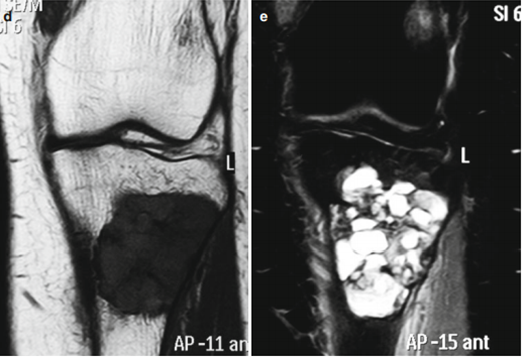

Рис.2: Бурые опухоли нижней челюсти, определяющиеся на рентгенограмме как очаги пониженной плотности в толще кости